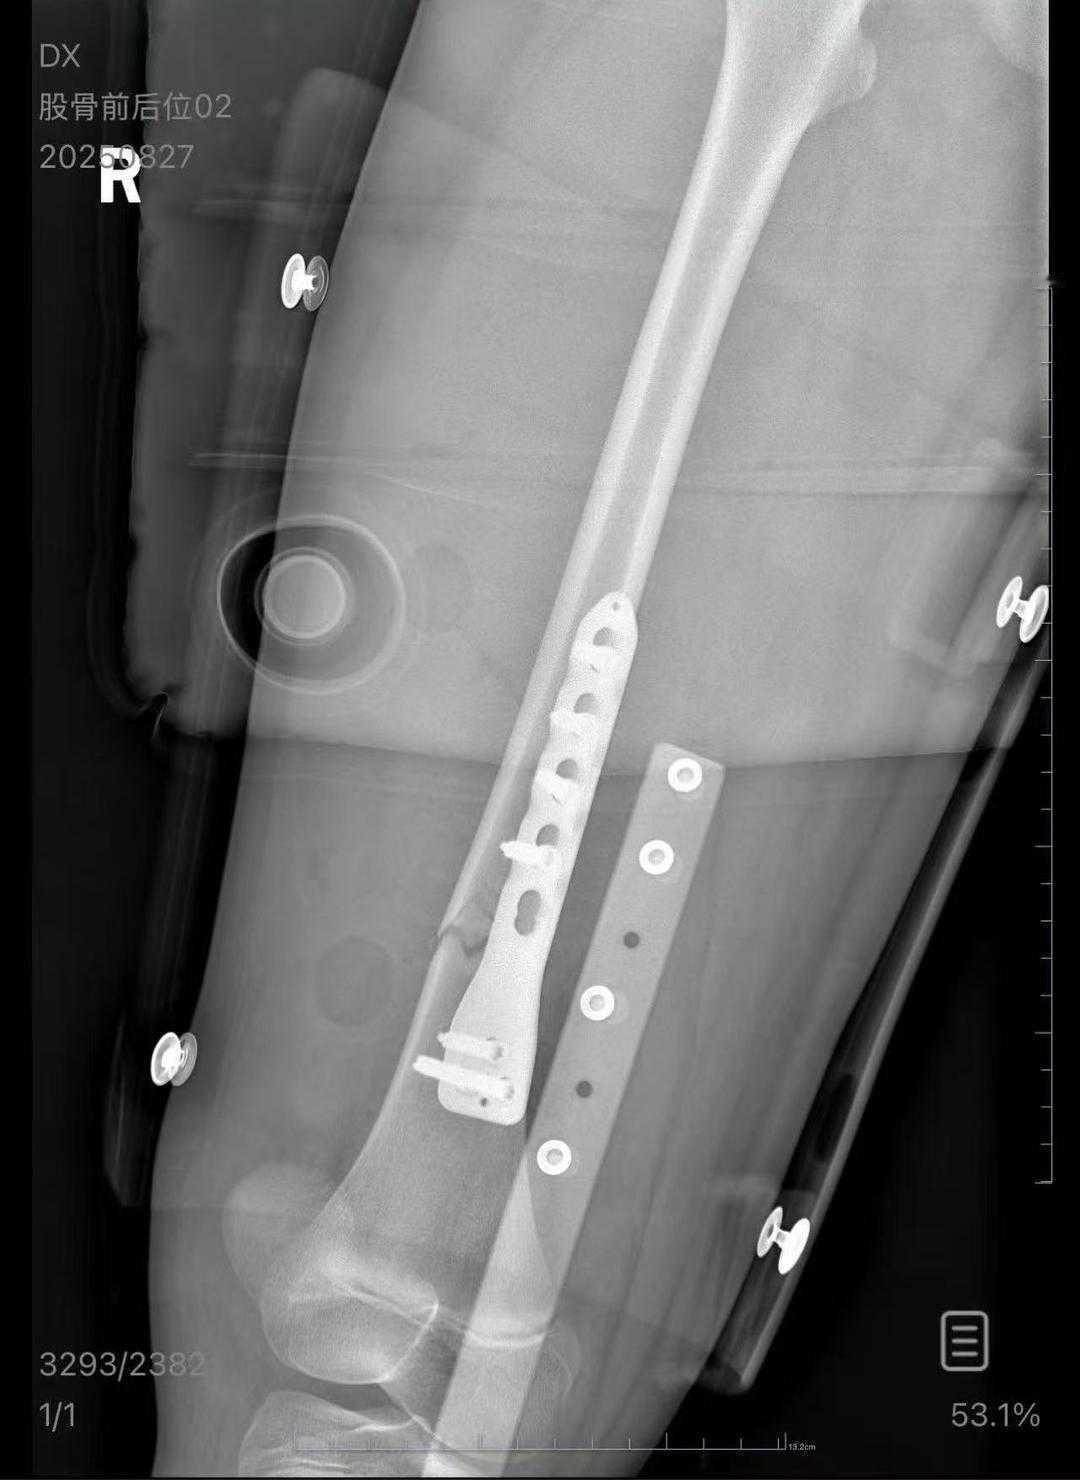

【火车卧铺“天降横祸”?男乘客跌落砸伤女孩后失联,家属 追责难】 本以为火车上的卧铺能让旅途更舒适,可朱女士的一家却在一次列车上遭遇意外——简直是“锅从天上来”。8月24日凌晨,朱女士带着10岁的女儿乘坐列车。当时快到无锡站时,一名男乘客在下铺位时没抓牢爬手,竟直接从上铺跌落,一头砸在女孩的大腿上,把孩子硬生生送进了医院。术后检查结果显示:女孩股骨骨折,不仅面临卧床康复的漫长过程,还可能留下未知的后遗症。 事故发生后,涉事男乘客表示要先回去筹钱赔偿,结果人影都找不到了,彻底“失联”。无助之下,朱女士只好打算通过法律渠道寻求公正。律师也分析,男乘客因为自身疏忽,对女孩的伤害负有直接责任。如果铁路方面在安全保障环节存在缺失,也有可能被一并追责。 这场突如其来的伤害,让人不禁反思卧铺列车的安全管理是否到位。乘客自身操作不慎固然是主因,但铁路部门是不是有更严格的防跌落措施?对于类似事件,律师建议家属一定要保留好全部证据,无论是医院诊断还是沟通记录,便于后续 追责。 这事儿谁都不愿碰上——孩子无辜受伤,家长心急如焚。也提醒所有出行的旅客:无论在高铁还是绿皮车上,安全意识绝不能松懈,尤其带娃出门,更要多一份小心。